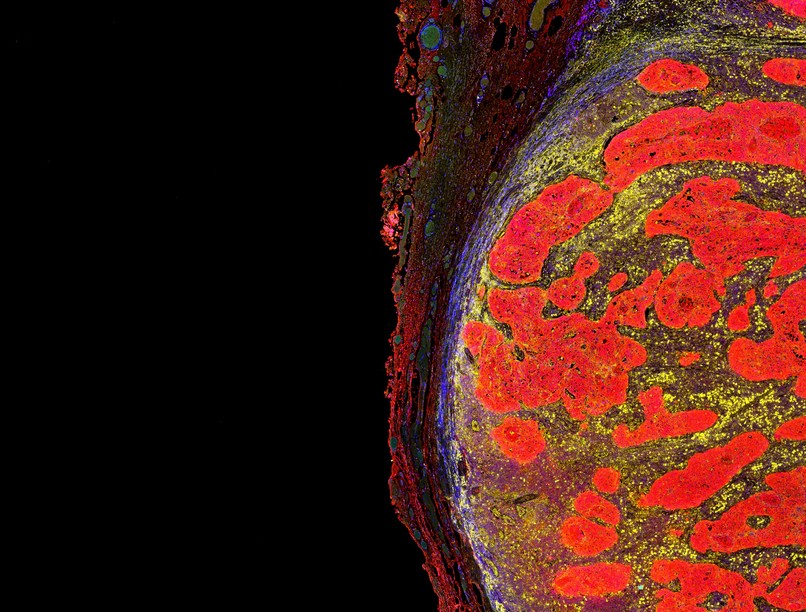

“Hideg” daganatokból “forró” tumorok

Az immunterápiák, mint például a pembrolizumab (Keytruda), olyan módon működnek, hogy gátolják a rákos sejtek által az immunrendszer T-sejtjeire gyakorolt gátló hatást. Azonban ahhoz, hogy ez hatékony legyen, a T-sejteknek képesnek kell lenniük behatolni a daganatba, hogy elvégezhessék feladatukat. Ez az, amit "forró" daganatoknak nevezünk, mint például a melanoma és egyes tüdőrákok, melyek egy alcsoportja jól reagál az immunterápiás kezelésekre.

Ugyanakkor sok más ráktípus, mint például az előrehaladott emlőrák és a hasnyálmirigyrák, "hideg" tumorokat alakít ki, amelyekben a T-sejtek nem képesek behatolni a daganat belsejébe. Ez a megértés lehetőséget adhat az új stratégiák kifejlesztésére az immunterápiás kezelések hatékonyságának javítása érdekében.